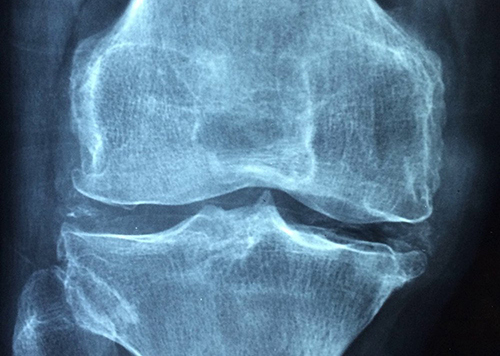

Исследователи из Медицинской школы Стэнфордского университета открыли способ регенерации хрящевой подушки суставов. Для этого сначала нужно нанести небольшое повреждение суставной ткани, а затем использовать химические сигналы для управления ростом скелетных стволовых клеток по мере заживления повреждений. Работа была представлена в журнале Nature Medicine.

В ее основе лежат предыдущие исследования Стэнфордского университета, в результате которых была выделена скелетная стволовая клетка, помогающая в производстве костей, хрящей и особого типа клеток. Чаще всего для лечения повреждений хрящей используется метод микроперелома. Поверхность сустава просверливается, что провоцирует тело создавать новую ткань, похожую на хрящ.

В рамках нового исследования ученые использовали молекулу, называемую костным морфогенетическим белком 2 (BMP2), чтобы инициировать формирование кости после микроповреждения. Процесс был остановлен на полпути с помощью молекулы, блокировавшей другую сигнальную молекулу, важную для образования кости, называемую фактором роста эндотелия сосудов (VEGF).

«В итоге мы получили хрящ, который состоит из клеток того же типа, что и натуральный, с сопоставимыми механическими свойствами, в отличие от фиброзного, получаемого обычно», - рассказывает доцент кафедры хирургии Чарли К.Ф. Чан. «Он также восстановил подвижность мышей с остеоартритом и значительно уменьшил их боль».